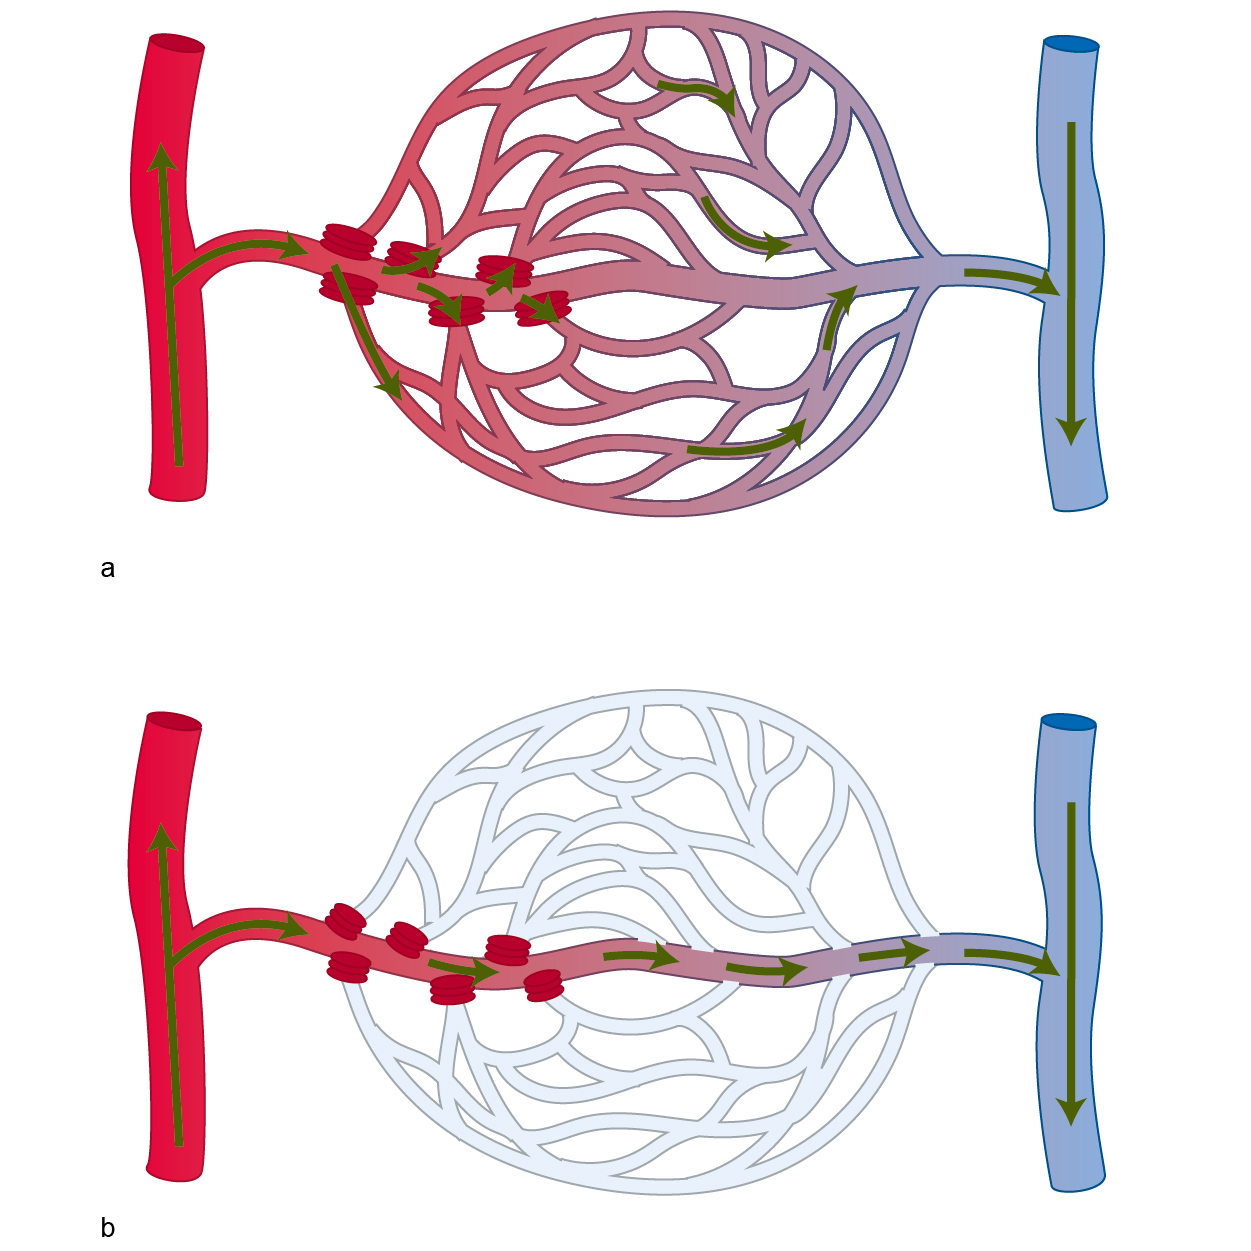

Herzlich willkommen! Ich bin Ihre Expertin für medizinische Illustrationen und kreative Kinderbuch-Illustrationen. Mit einem Auge für wissenschaftliche Genauigkeit und einer Liebe zur Gestaltung kindgerechter Erzählwelten schaffe ich Bilder, die informieren und begeistern. Entdecken Sie mein Portfolio und lassen Sie sich von meiner Arbeit überzeugen!